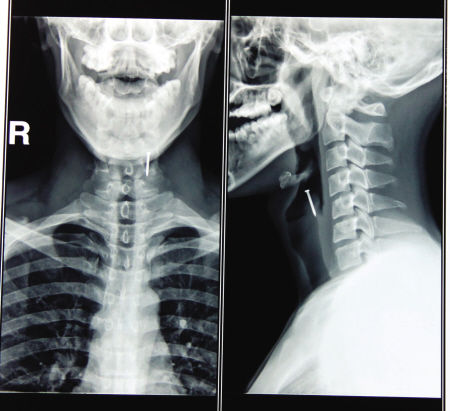

医院里,小刘大张着嘴,脖子僵硬不敢转动。由于钉子已经卡在喉咙里4个小时了,此时,他的脸色发白,头上渗着汗珠。五官科的关志华医生检查后发现,这根长约3厘米的铁钉,经过几番折腾,已经深深“钉”在了小刘的喉咽黏膜里,只剩一个螺帽裸露在外。

该如何救治?最终,关医生决定对小刘进行咽部局部麻醉,并用异物钳将钉子从其咽部顺利拔出。术后他对小刘进行再次检查,没有发现因为手术而损伤到周围的咽喉部。给其服用消炎药后,小刘就顺利出院了。